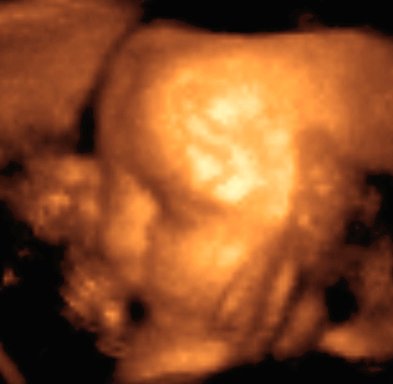

Folosind ultrasunete cu frecventa de ordinul megahertzilor, poate fi investigat in detaliu interiorul organismelor vii, fara a le afecta prea mult (ecograful).

La granita dintre doua tesuturi cu consistenta diferita, se produce reflexia ultrasunetelor (ecou).

Un computer interpreteaza ecourile sosiste si genereaza o imagine tridimensionala a obstacolelor intalnite.

Astfel, poate fi vazut un copil inainte ca acesta sa se nasca ! (figura 1D5−2)

Fig. 1D5−2. Imaginea unui copil nenascut inca, obtinuta cu ecograful tridimensional.